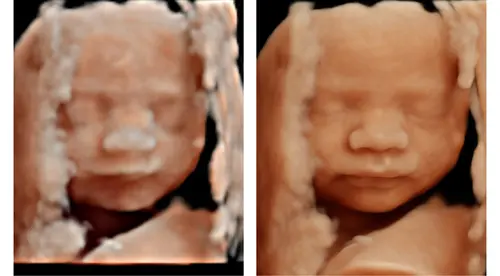

Bij ons lag ze zo lastig dat er maar 1 enigszins normale foto kon worden gemaakt. We mogen maandag voor de herkansing en morgen bij een meisje in opleiding. Dus nog 2 kansen voor hopelijk een beter beeld van onze dochter.